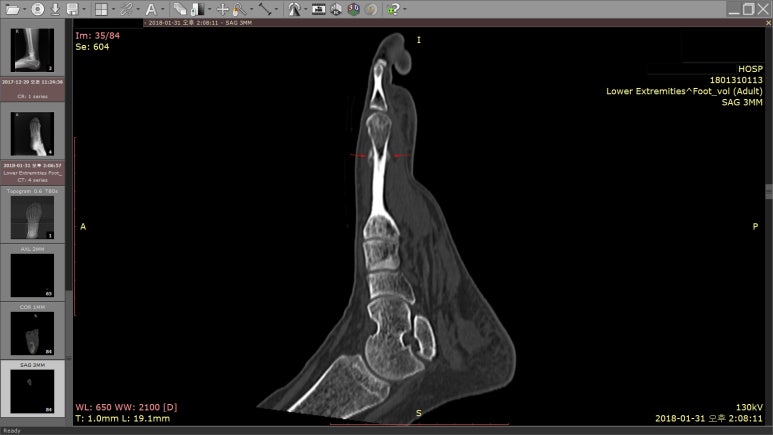

다시 찍어본 X-RAY에서

골절 후 흔적인 가골(bone callus)이 보였고,

정확하게 확인하기 위해 CT 검사를 받았습니다.

빨간 화살표로 표시한 부분이 발가락이 골절 됐던 곳입니다.